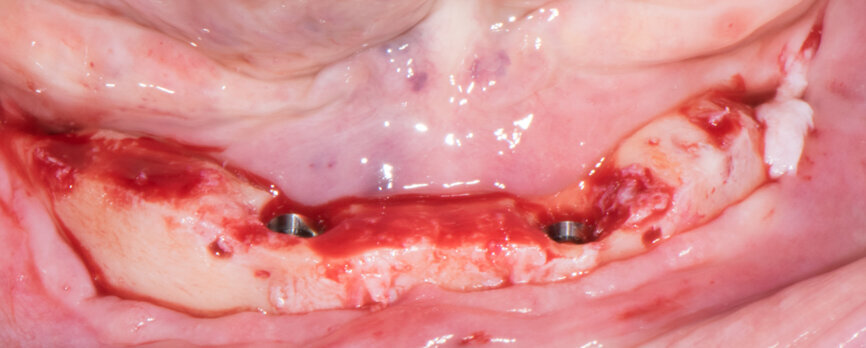

Implant beds were prepared (Figs. 13 & 14) and Straumann BLT implants placed with a torque setting of more than 35 Ncm, following the protocol to allow correct subsequent screw retained abutment placement (Figs. 15 & 16). Bone around the implants was prepared with bone profilers (Straumann) for the same reason (Fig. 17). The crest was flattened (Figs. 18 & 19), screw-retained abutments were screwed to 35 Ncm (Fig. 20) and covered with healing caps, and the wound was sutured (Fig. 21).